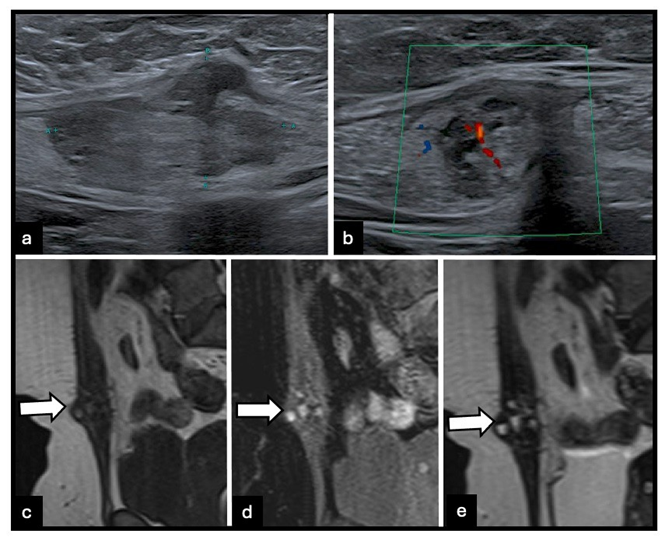

MRI is the reference standard for evaluating abdominal wall and intramuscular endometriosis. Imaging features vary according to lesion composition. Predominantly fibrous lesions exhibit low to intermediate signal intensity on T2-weighted images, often with ill-defined margins and infiltrative growth patterns (Figure 1). Intramuscular cystic lesions may be well-circumscribed, occasionally resembling ectopic ovarian endometriomas (Figure 2). Infiltrative intramuscular lesions with hemorrhagic microcysts present as punctate or confluent hyperintense foci on fatsuppressed T1-weighted images (Figure 3). Overall, lesions can be iso- to hyperintense relative to muscle on T2-weighted images, with focal T1 hyperintensity reflecting hemorrhagic components, a feature highly suggestive of endometriosis. [3,5] After gadolinium administration, lesions usually demonstrate moderate to marked, often heterogeneous, enhancement. Lesions may appear nodular, spiculated, or retractile and can infiltrate adjacent muscular layers, including the rectus abdominis or oblique muscles. Diffusionweighted imaging often demonstrates intermediate diffusion restriction, with reported apparent diffusion coefficient (ADC) values around 0.93 × 10⁻³ mm²/s. [5] MRI also permits accurate delineation of lesion extent through the abdominal wall layers and facilitates detection of concurrent pelvic disease, which is essential for comprehensive surgical planning [3,5].

Figure 3: 51-year-old woman with infiltrative intramuscular abdominal wall endometriosis involving the right rectus abdominis muscle. (a) B-mode ultrasound image shows a parietal intramuscular lesion. (b) Color Doppler ultrasound image demonstrates mild hyperemia. (c) Sagittal T1-weighted MRI image shows slight hyperintensity (arrow). (d) Fat-suppressed T1-weighted MRI image demonstrates punctate and confluent foci of marked hyperintensity, reflecting hemorrhagic microcysts (arrow). (e) Sagittal T2-weighted MRI image shows iso- to moderately hyperintense signal relative to muscle (arrow), consistent with infiltrative endometriosis.